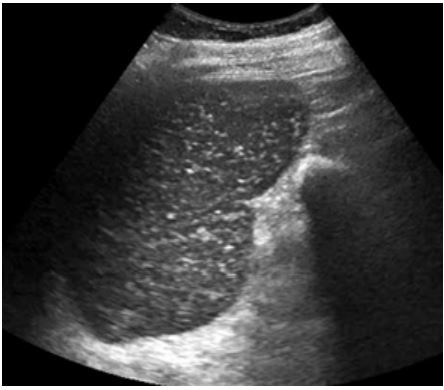

Homem de 68 anos refere diversos episódios prévios de hemorragia digestiva alta por varizes esofágicas. Conta ter tratado esquistossomose há muito tempo. Diz que o seu baço é grande há vários anos. Na ultrassonografia de abdome, foram evidenciadas imagens no parênquima esplênico (foto). A que correspondem essas imagens?

Provas